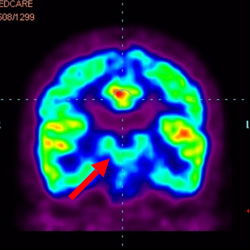

細胞治療前 PET CT 掃描顯示神經(jīng)組織中的藍/黑色區域,表明腦癱引起的大腦損傷。

細胞治療后,藍色和黑色區域減少,并且看到更活躍的區域。這表明損傷減少并改善了大腦功能。

這證明細胞療法是治療腦癱兒童安全有效的方法。細胞療法可以更新大腦損傷的核心,并且可以通過(guò) PET CT 掃描來(lái)監測大腦的改善情況。這些細胞療法與標準治療一起促進(jìn)腦癱兒童的生長(cháng)和改善。